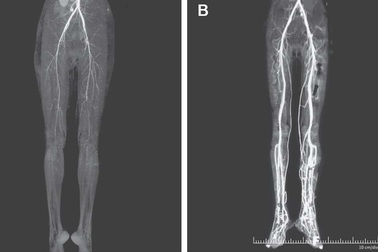

Người phụ nữ mắc căn bệnh cực hiếm có tên "Lửa thánh" thời trung cổTheo báo cáo trên Tạp chí Y học New England, một phụ nữ đã được chẩn đoán mắc một căn bệnh thời trung cổ cực hiếm được gọi là "Lửa thánh" hay "Lửa St Anthony", sau khi trải qua cơn đau rát ở chân.